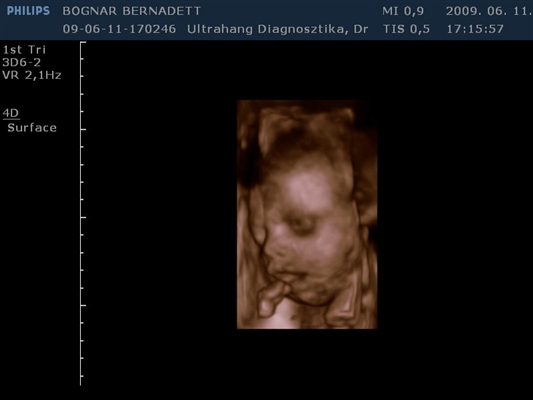

Kb. 3,5 hete én is voltam 4D-n és egy egész jó kis kép kerekedett belőle, majd felteszem.